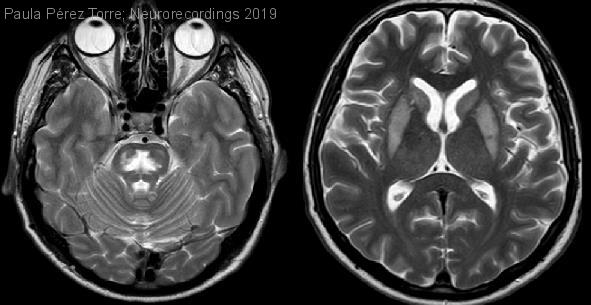

Parkinsonismo agudo como forma de presentación de mielinolisis central pontina y extrapontina tras adecuada corrección de hiponatremia.

Diagnóstico final: Mielinolisis central pontina/extrapontina

Varón de 50 años , hipertenso en tratamiento con tiazidas. Acudió a Urgencias por mareo y en la analítica de sangre se descubrió un sodio de 103 mEq/L. Se inició una corrección lenta con un...